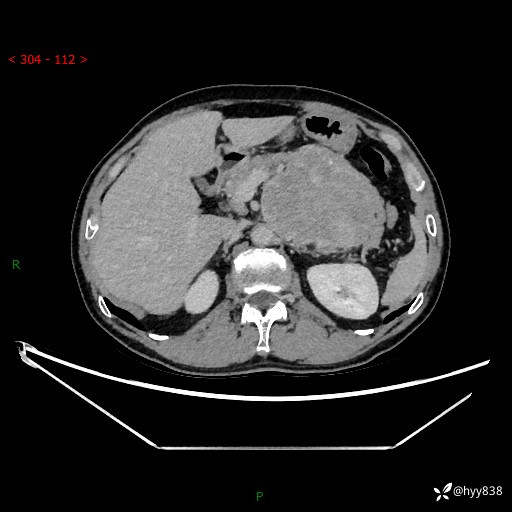

年龄:61岁

主诉:发现腹膜后肿瘤3天

腹部CT平扫+增强(动脉期+静脉期)